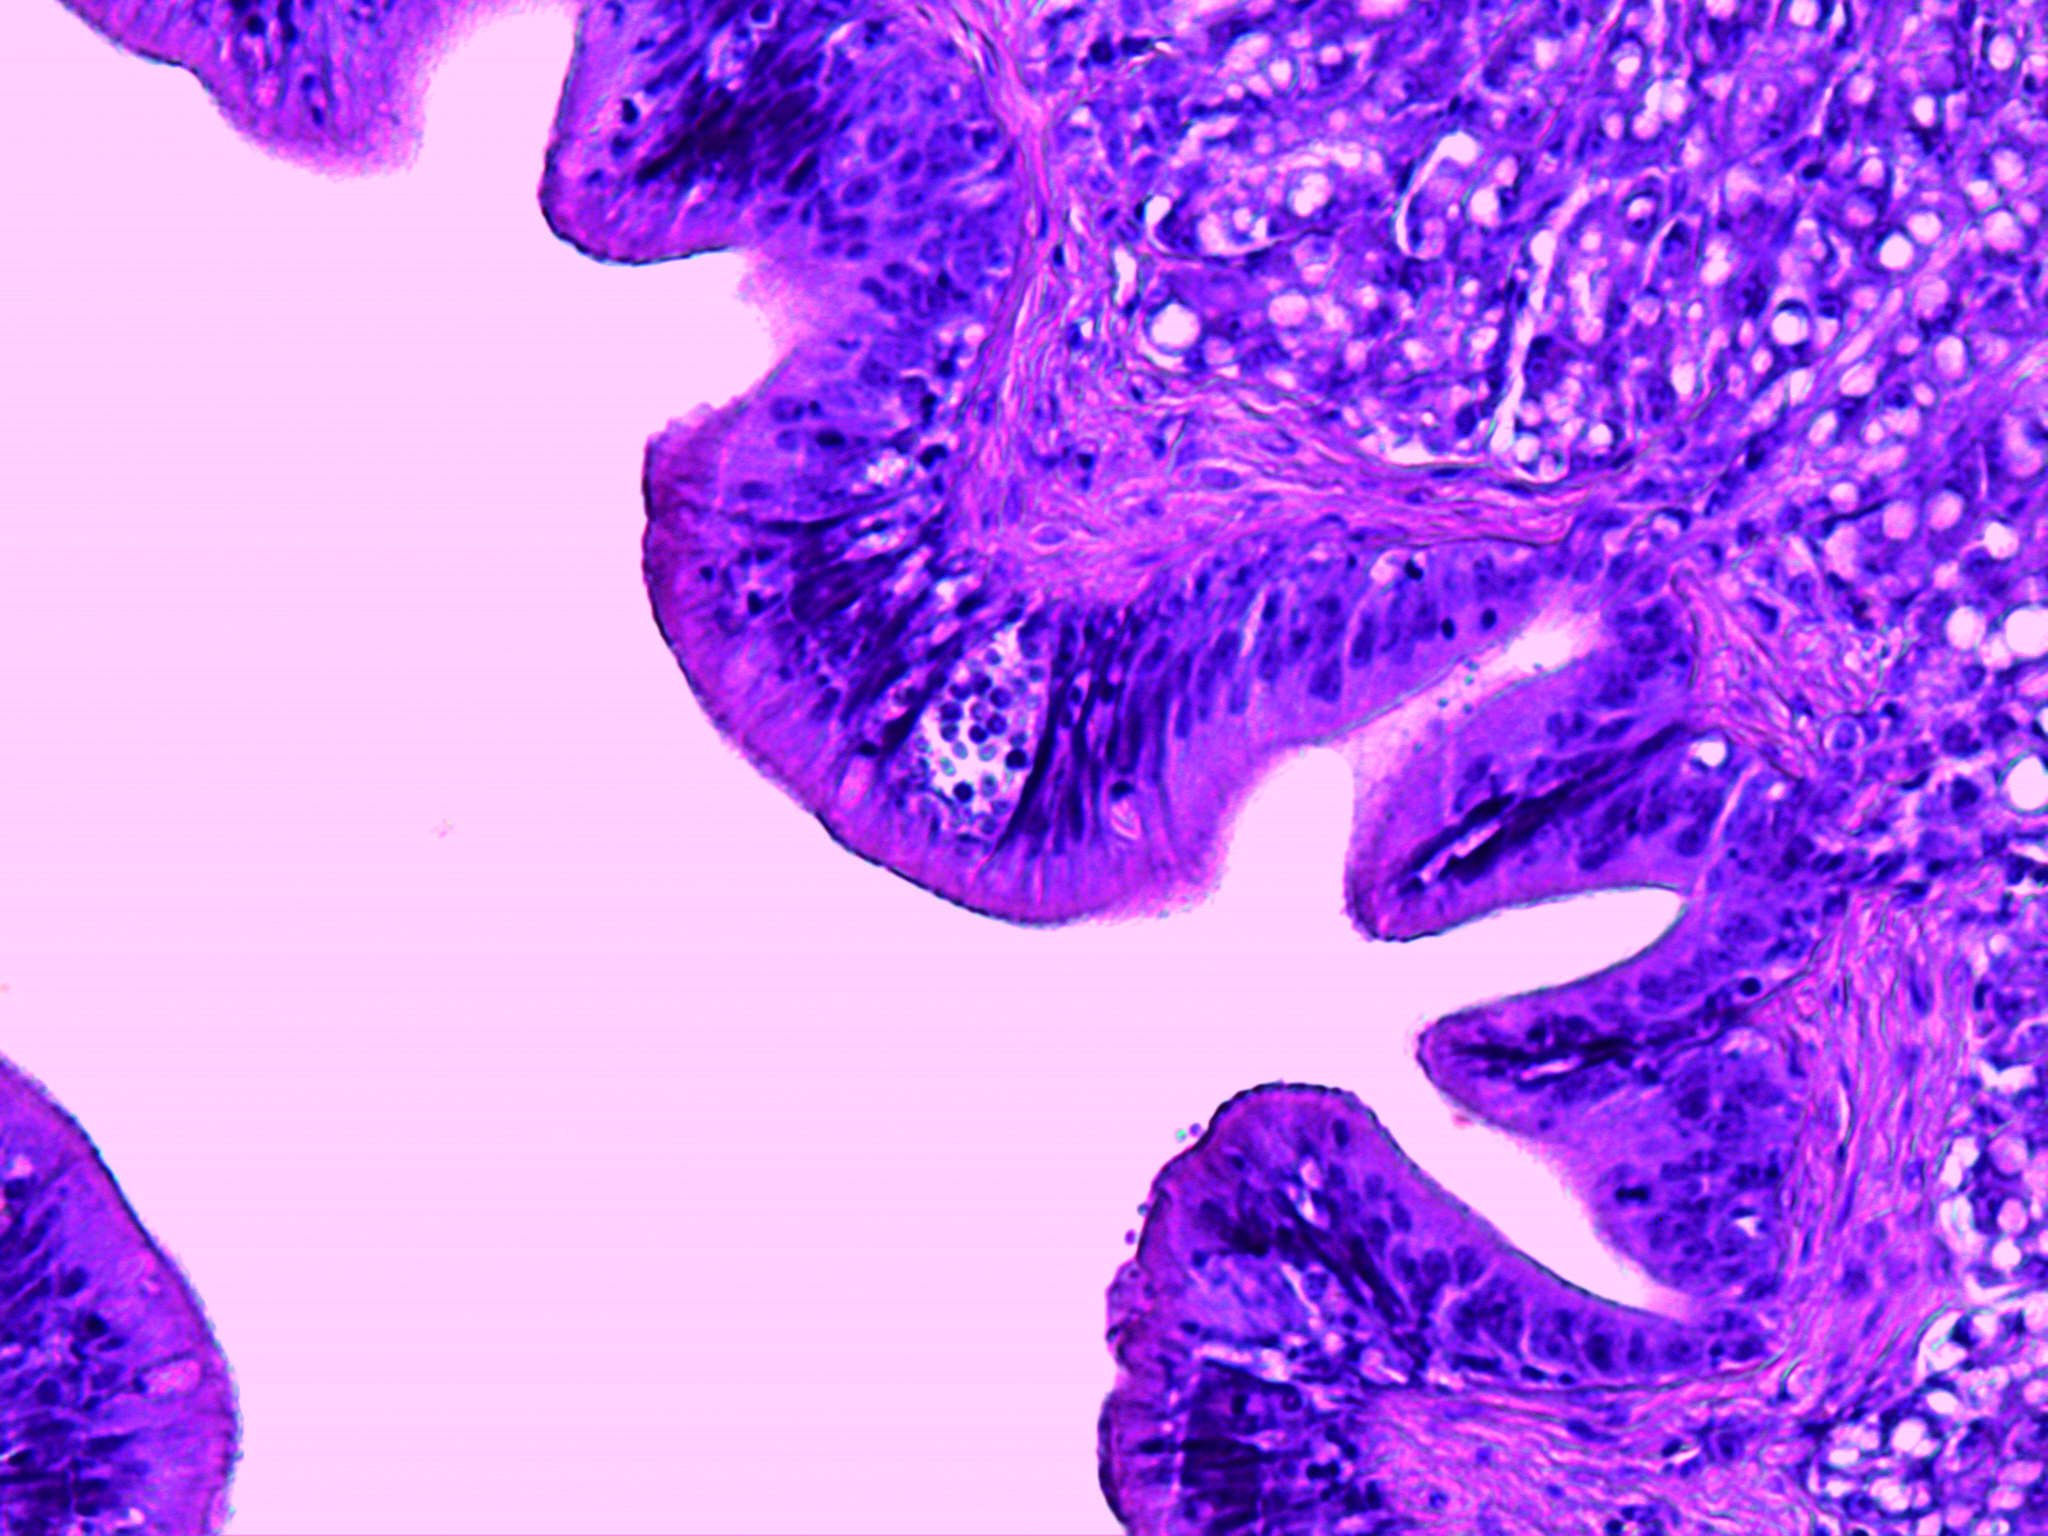

Epitheliocystis

Agent: Order Chlamydiales (Obligate intracellular bacterial pathogens). Traditionally, bacteria from the phylum Chlamydiae were the only known pathogenic agents, but etiology is now recognized as being more complex, including a range of Proteobacteria.

Symptoms: Sea bream and, less commonly, sea bass are affected. Caused by an intracellular bacterium that replicates within gill epithelial cells, leading to hypertrophy and that compromise gill function. Severe infections may cause hyperventilation and mortality.

Control: Antibiotic therapy response is variable. No vaccine is available.